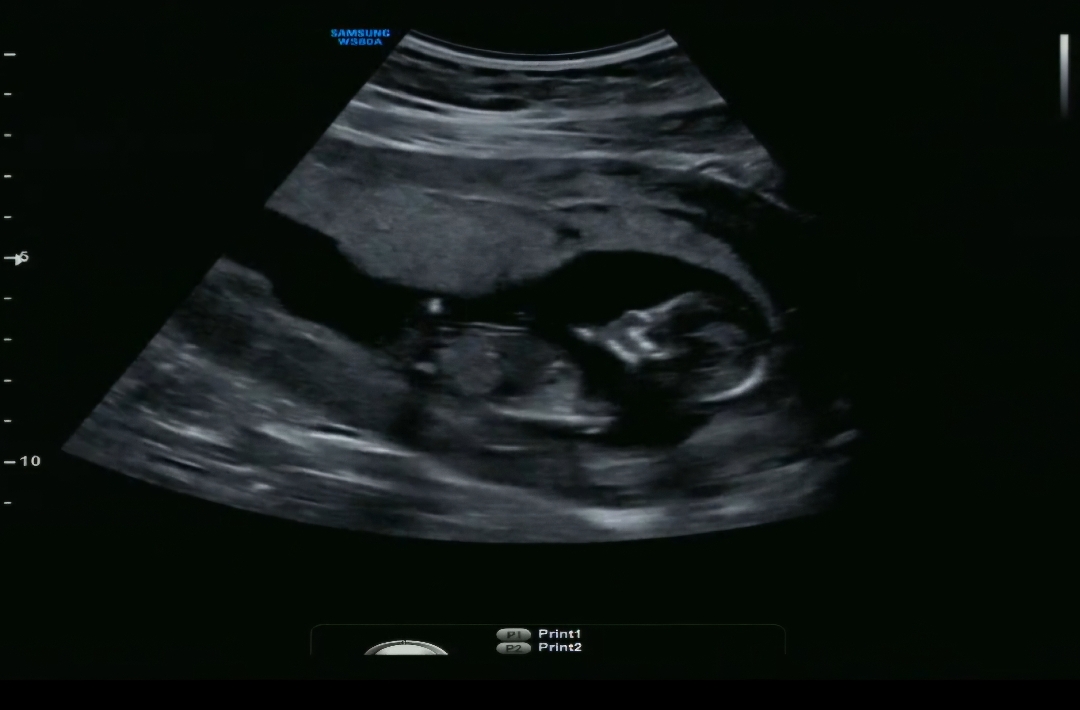

12주4일차 각도법 참견부탁드려요🫶

참견부탁드려용😊